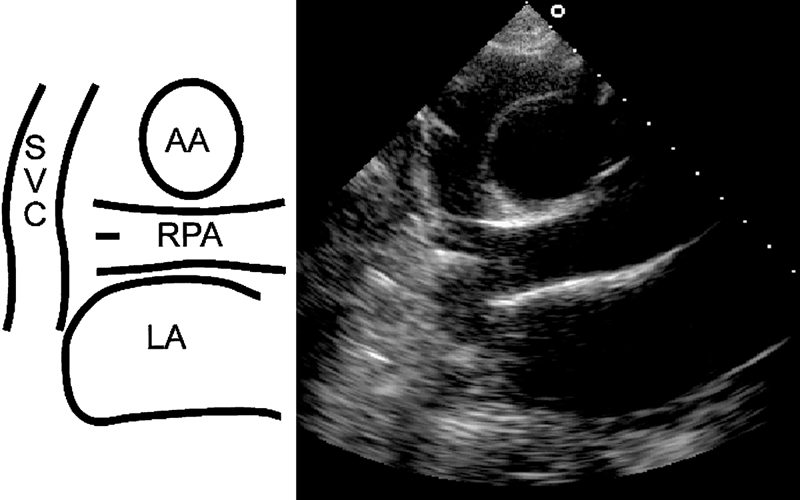

فحوصات تشخيصية لبعض امراض القلب والشرايين التاجية